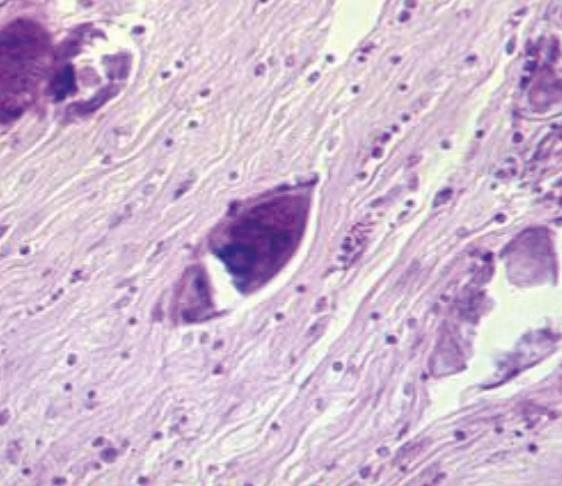

Иллюстрация к книге — Аллергия. Истинные причины. Лечение [i_018.jpg]

Рис. 15. Яйца кровяной шистосомы (фото биопсии мочевого пузыря)